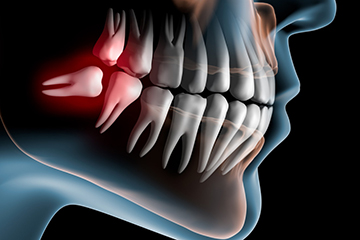

Le indicazioni all'asportazione di un terzo molare in inclusione totale o parziale sono diverse a seconda che il dente sia o meno associato a segni o sintomi.

Nel caso in cui il terzo molare sia sintomatico, le indicazioni cliniche all'estrazione sono rappresentate da pericoroniti, dente non recuperabile per carie, frattura, lesioni parodontali o endodontiche non trattabili, infezioni acute o croniche ( ascessi e celluliti), anomalia della forma e della grandezza del dente tali da provocare delle malfunzioni e malposizione che provoca disagio. In assenza di sintomatologia, le indicazioni alle estrazioni sono: prevenzione di un danno parodontale sul secondo molare, facilitare una terapia parodontale, facilitare una riabilitazione protesica, facilitare movimenti ortodontici, presenza di un dente che si trova in una rima di frattura ossea, dente che si trova coinvolto in una zona di escissione neoplastica, interferenza del dente con chirurgia ortognatica e/o ricostruttiva, rimozione preventiva e/o profilattica in pazienti con problematiche mediche maggiori oparticolari condizioni chirurgiche o trattamenti terapeutici, rifiuto consapevole del paziente di un trattamento non chirurgico, nei soggetti che praticano sport con elecvate probabilità di traumi (es. pugilato, sci, rugby, etc.), nei soggetti con meno di 25 anni di età per ridurre la probabilità di danno parodontale del secondo molare associate all'asportazione tardiva.

Importanti ed imprescindibili sono, inoltre, gli esami radiografici perché definiscono l'esatta posizione dell'elemento dentario ed i suoi rapporti di continuità con le strutture anatomiche adiacenti. L'esame radiografico di base è rappresentato dall'OPT; possono anche essere effettuate Rx endorali e, qualora fosse necessario avere informazioni più precise, la TC o la Rx tridimensionale a fascio conico.